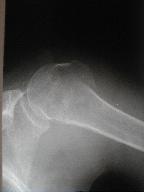

上腕骨頚部骨折 その3

現在、日常動作にはなんら支障なく生活している